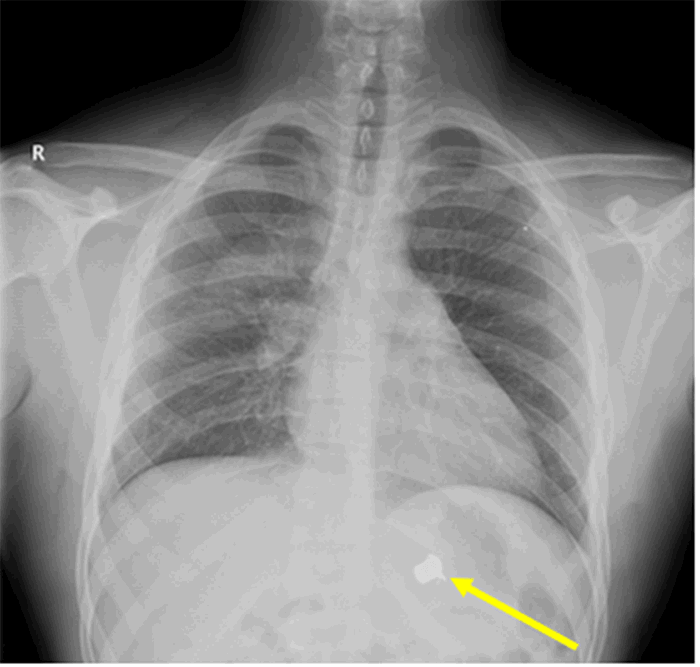

A final follow-up chest X ray (Figure 5), obtained three weeks after the injury, shows resolution of the lung injury with the bullet still positioned in the left diaphragmatic sulcus. We did consider performing a video-assisted thoracoscopic bullet retrieval, as has been previously described,11 but opted not to as the bullet was not causing ongoing pain or inflammation.

Figure 5. Follow-up chest X ray of patient with Transmediastinal gunshot wound. Solid yellow line indicates the position of the bullet on X ray.